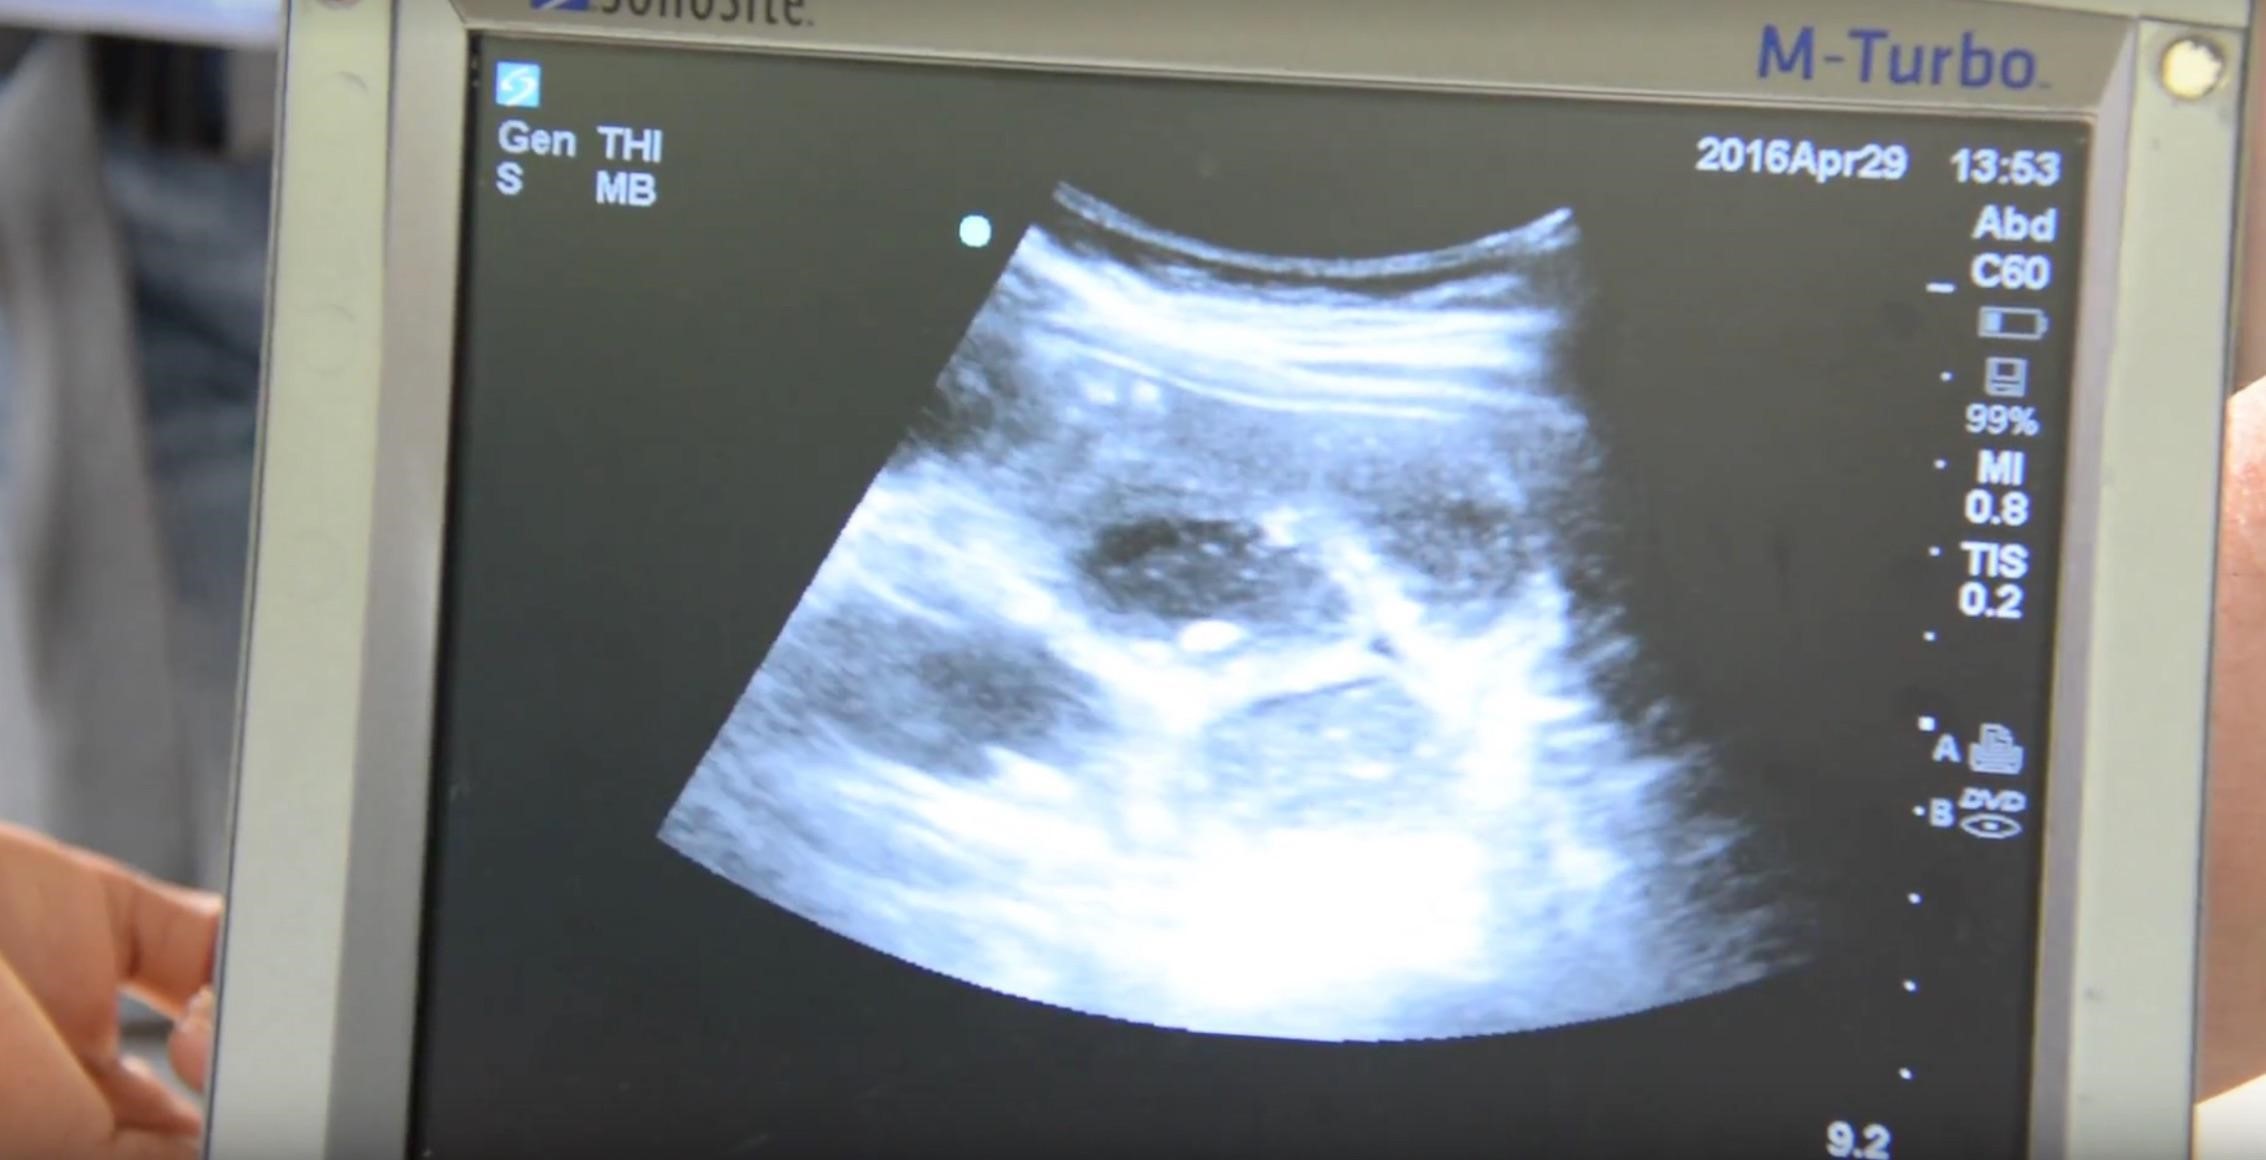

We present the case of a 15-year-old female patient with no known past medical history who presented to a transient medical clinic in the remote territory of La Moskitia, Honduras with a three-month history of poor appetite, nausea, vomiting, and worsening epigastric pain. She was initially diagnosed as gastritis at an external clinic. However, a point-of-care ultrasound examination was performed, and she was diagnosed with a small bowel obstruction (SBO) (Figure 1). During her visit, she had an episode of emesis, which demonstrated a large worm consistent with an Ascaris lumbricoides (Figure 2). The etiology of the SBO was suspected to be secondary to physical obstruction from the Ascariasis obstruction.

Figure 1. Portable ultrasound that was used to diagnose a small bowel obstruction.

Ultrasonography has been shown to be a useful adjunct in the evaluation of patients with suspected SBO as it can be performed rapidly and with high accuracy, even when performed under minimal training.6,7 The diagnosis is made based upon a small intestinal diameter of greater than 2.5 cm with abnormal peristalsis.6 A recent systematic review and meta-analysis found that ultrasound was 92.4% sensitive and 96.6% specific with a positive likelihood ratio of 27.5 and a negative likelihood ratio of 0.08.8 Therefore, ultrasound can be a valuable adjunct for making the diagnosis and is particularly valuable in areas where access to advanced imaging is limited. In this case, ultrasound was able to make the diagnosis and lead to transfer to an advanced healthcare facility, which may not have otherwise been possible.